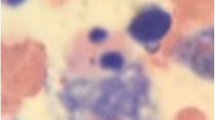

Persistence of the two mutants as mannose-rich glycosylated species is suggestive of an ER localization of the two protein variants. To substantiate these results using a different procedure, we analyzed the intracellular localization of the mutants by confocal immunofluorescence microscopy. As shown in Figure 2, wild type LPH is located in the ER and the Golgi apparatus as well as at the cell surface, while both mutant variants were predominantly located in the ER as assessed by the typical ER net-like structures.

Intracellular localization of wild type and the mutants in COS-1 cells. For visualization of LPH, transiently transfected COS-1 cells, expressing the wild type LPH, LPH-Y1473X or LPH-D1796fs, were fixed with 4% paraformaldehyde and permeabilised with 0.5% saponin. Immunolabeling was carried out using mAb anti-LPH (1:1000) as the primary antibody and anti-mouse IgG conjugated with Alexa 488 as the secondary antibody (1:500). The samples were analyzed by confocal laser microscopy.